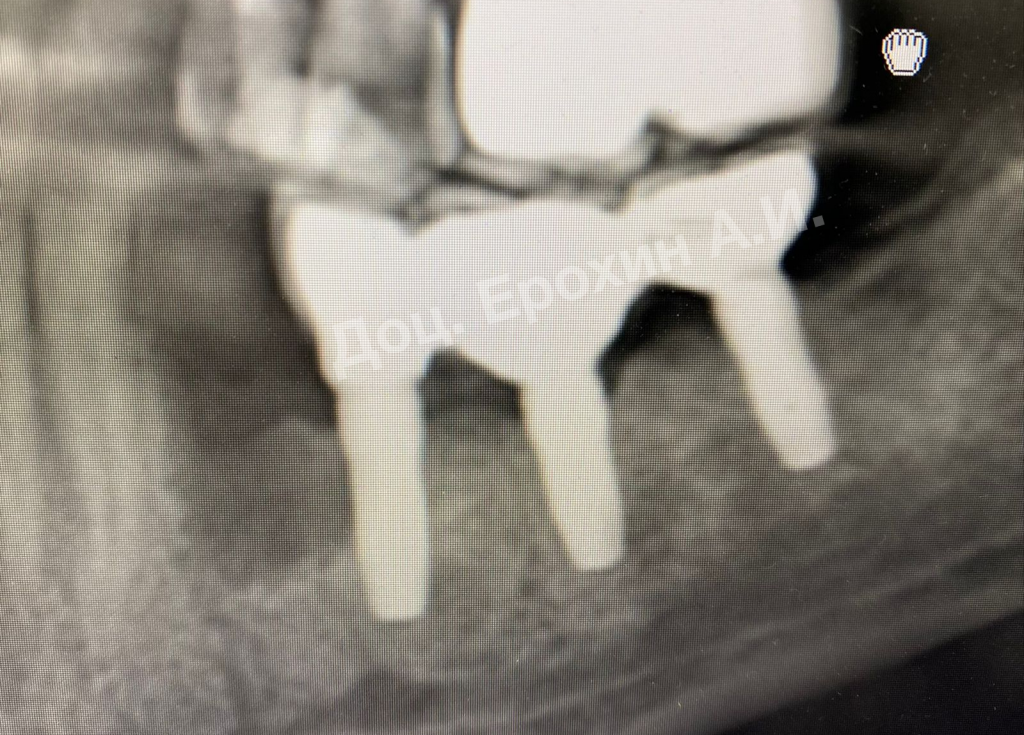

Вертикальные аугментации — самый непредсказуемый тип костной пластики методом НРТ. Мембрана способна коллапсировать, смещая в апикальном направлении костный материал, тем самым полностью нивелирую потраченные усилия.

Тентовые винты имеют широкие шляпки, которые позволяют мембране опираться на них, тем самым препятствуя изменению профиля регенерируемого участка.